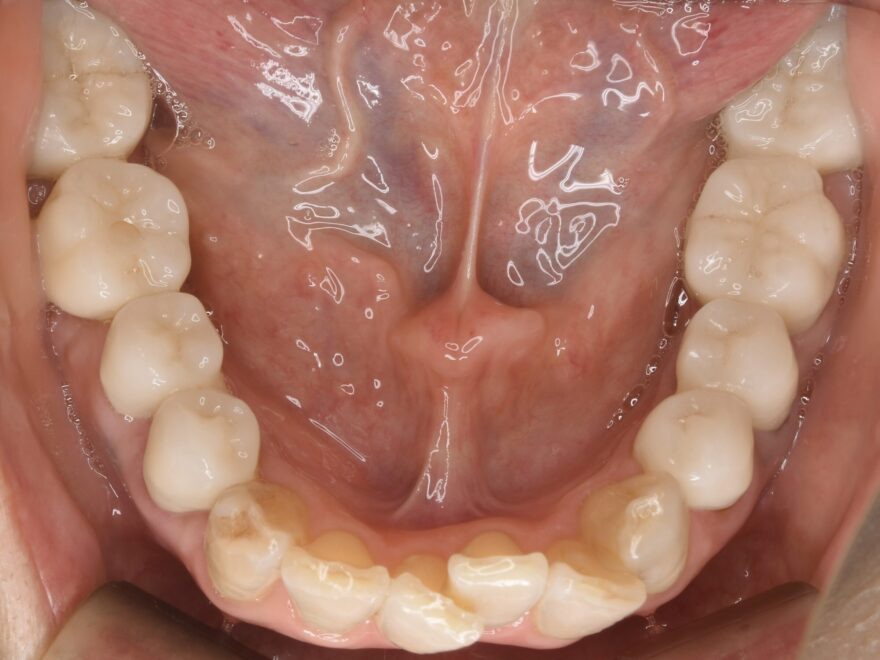

治療後の口腔内写真

こちらにも、何でも噛める機能的なセラミック歯が入りました。。

こちらも、どこにインプラントが入っているか分からない自然な形態を再現できました。